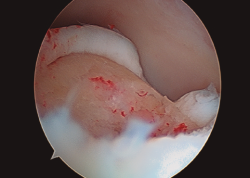

Figura 2. Técnica de estimulación medular con nanofracturas. Obsérvense los bordes del curetaje y la cruentación de la capa mineralizada.

- Posteriormente, realizamos la técnica de estimulación seleccionada entre: brocado o microperforaciones o nanoperforaciones. Preferimos realizar estas últimas a perforaciones más grandes que pueden dañar el hueso subcondral u otras técnicas de brocado con agujas de Kirschner que pueden producir necrosis inducida por el efecto térmico (Figura 2). Cada “nanofractura” debe realizarse separada 3-4 mm con una profundidad de 9-10 mm y un diámetro de 1 mm.